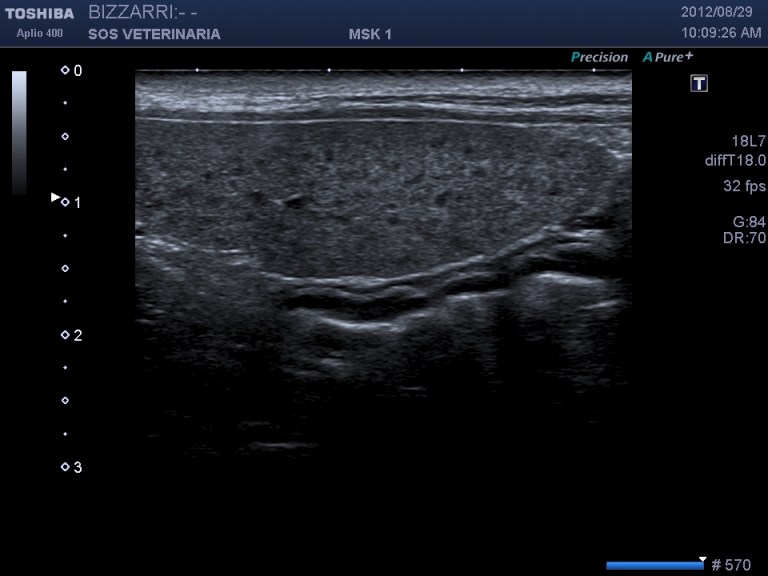

In questo caso clinico la patologia era rappresentata da una virosi con segni clinici tipici di vomito diarrea e leucopenia ,il referto dell’ascaridiosi (come spesso accade) era del tutto occasionale o al massimo un fattore complicante il decorso della malattia.

L’ascaride si differenzia ecograficamente dal copo estraneo filiforme per la presenza della parete esterna (cuticola) ,una parte interna parenchimale e l’assenza di cono d’ombra ,inoltre l’intestino puo’ essere spastico ma mai circonvoluto con pattern a fisarmonica.